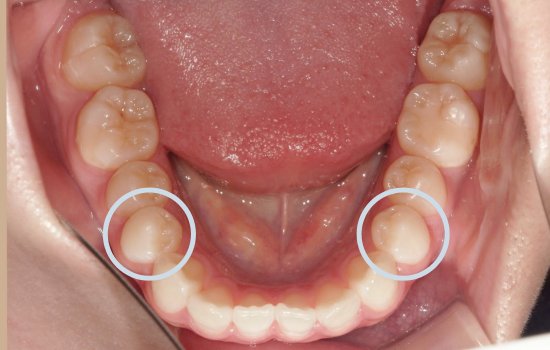

<初診時>

一見すると大きなガタガタはなく、歯並び自体は比較的きれいに整っているように見えます。

角度を変えて確認すると、上の前歯が前方に突出しており、上下の前歯がしっかり噛み合っていない状態(前歯部に隙間)が認められました。

このように、歯列の乱れは軽度である一方、前歯の前突および口元の突出感が認められました。

「口元をしっかり引っ込める」ためには、前歯を十分に後方へ移動させる必要があります。今回は、上下左右の第一小臼歯(4番)を抜歯しました。

この抜歯によってできたスペースを利用し、前歯を後方へ引き下げていきます。

この症例では、下あごが小さい(下顎後退症)、下あごの歯の周囲の骨が薄いという骨格的特徴があり、上あごと下あごで「歯を動かせる量」に差がありました。